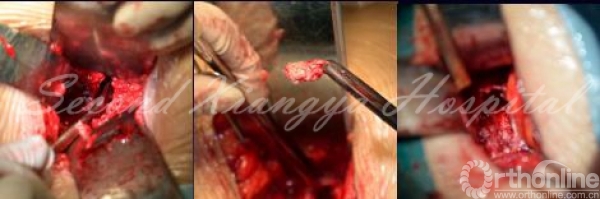

10.术后患者症装完全缓解,复查见突出部分的间盘已经摘除,融合器位置良好。

术后X线

术后复查